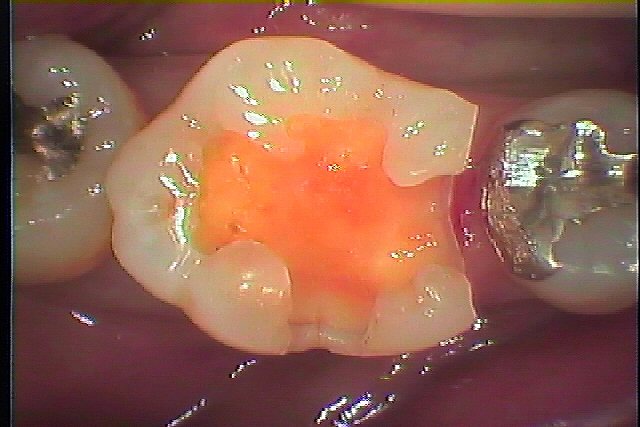

虫歯を除去して行きます

黒い虫歯がなくなりました